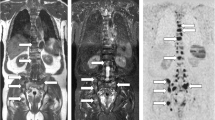

Bone metastases from prostate cancer are a well-established example of osteoblastic metastases [9, 13, 16] (Fig. 2). In prostate cancer, prostate-specific antigen (PSA) inhibits parathyroid hormone-related peptides, which leads to the enhancement of osteoblast function [9, 11, 17]. However, the development of various imaging modalities has enabled the detection of other types of metastases, such as mixed or inter-trabecular types (Fig. 3).

Mixed-type/intertrabecular metastases. A 78-year-old man with a 4-year history of prostate cancer and transition to castration-resistant prostate cancer (CRPC). Serum PSA was 5.954 ng/mL. a On T1W image, multiple low-intensity areas are shown, including in the Th8 and Th11 (white arrowheads). b On the DW sagittal reconstructed image, multiple high-intensity areas are shown, including in the Th8 and Th11(arrowheads). c On the CT reconstructed sagittal image, obvious sclerotic or lytic changes were not observed. In fact, the diagnosis of multiple bone metastases using only CT examination was not possible. These CT findings were defined as intertrabecular metastases

2. Primary mixed-type metastases/inter-trabecular metastases (Fig. 3).

Other types, such as osteolytic and inter-trabecular types, are also detectable.

In this case, CT images do not show the abnormal findings, such as bone formation or destruction, and DWI of MRI show high signal intensity.